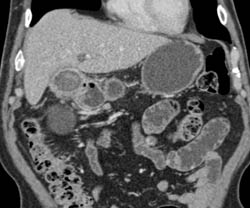

Neuroendocrine Tumor With Nodes Near IVC